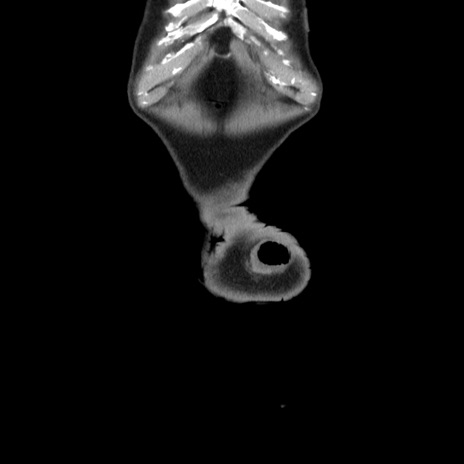

症例24(冠状断像)

横断像